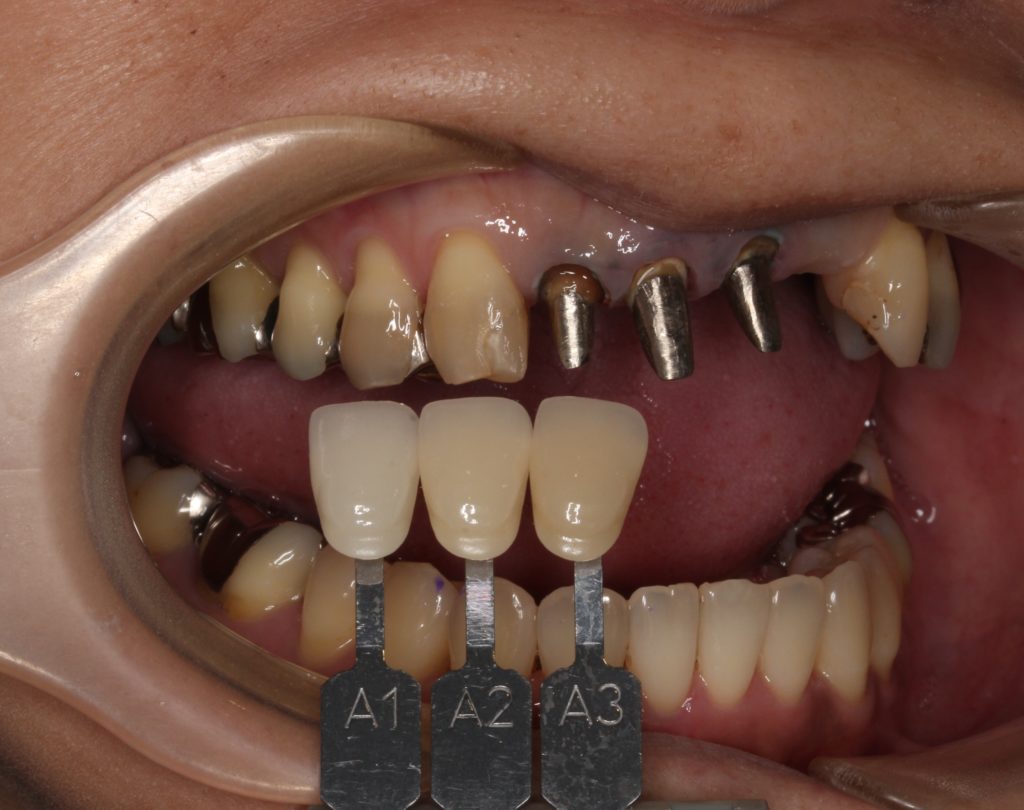

このような状態です。

金属の支柱(コア)がしっかりと入っています。

新しいかぶせ物が入るように形を整えます。

歯の色見本で、周囲の歯の色に合わせます。

人それぞれ歯の色が違います。指紋のようなものですね。

また歯の場所によっても色は違い、1本1本グラデーションが出ていています。